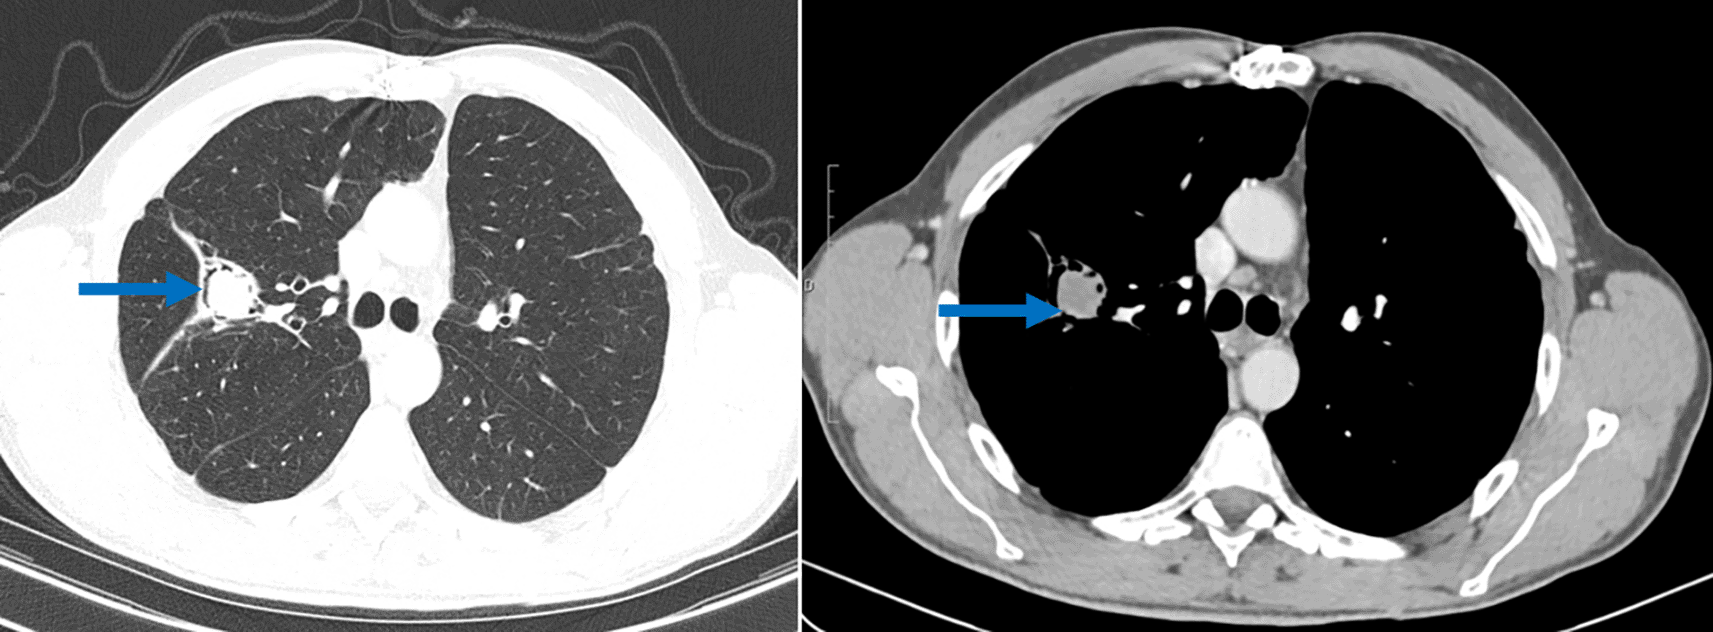

During regular post-surgical follow-up, a scannographic imaging revealed fluid-density endo-bronchial material in the right superior lobe (lung cavity sequelary to the previous cystectomy) separated from the cavity wall by airspace (“air crescent” sign). This image was typical of pulmonary aspergilloma (Figure 3). Although the Aspergillus serology showed doubtful results, the clinical context together with the CT scan findings were highly suggestive of a pulmonary aspergilloma. Blood tests showed high levels of IgE. A surgical resection of the cavity was scheduled but not yet performed.

Another intriguing finding in this case report was the discovery of an aspergilloma, on the lung cavity. Pulmonary aspergilloma occurs as a colonizer of pre-existing pulmonary cavity of any etiology such as tuberculosis sequelae, cavitary neoplasia or operated hydatid cyst and it is a saprophytic infection.11 Aspergilloma has rarely been described in operated hydatid cyst cavities in immunocompetent patients.12 For this patient, the aspergilloma was discovered two years after the lung surgery. A very similar case of a 56-year-old patient, who presented with an aspergilloma of the upper right lobe following cystectomy, have been reported by M. El Hammoumi et al.12